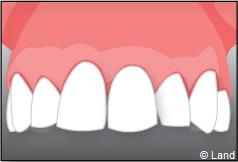

Exemple d’une réhabilitation complète implantaire

Situation clinique initiale

Situation clinique terminée